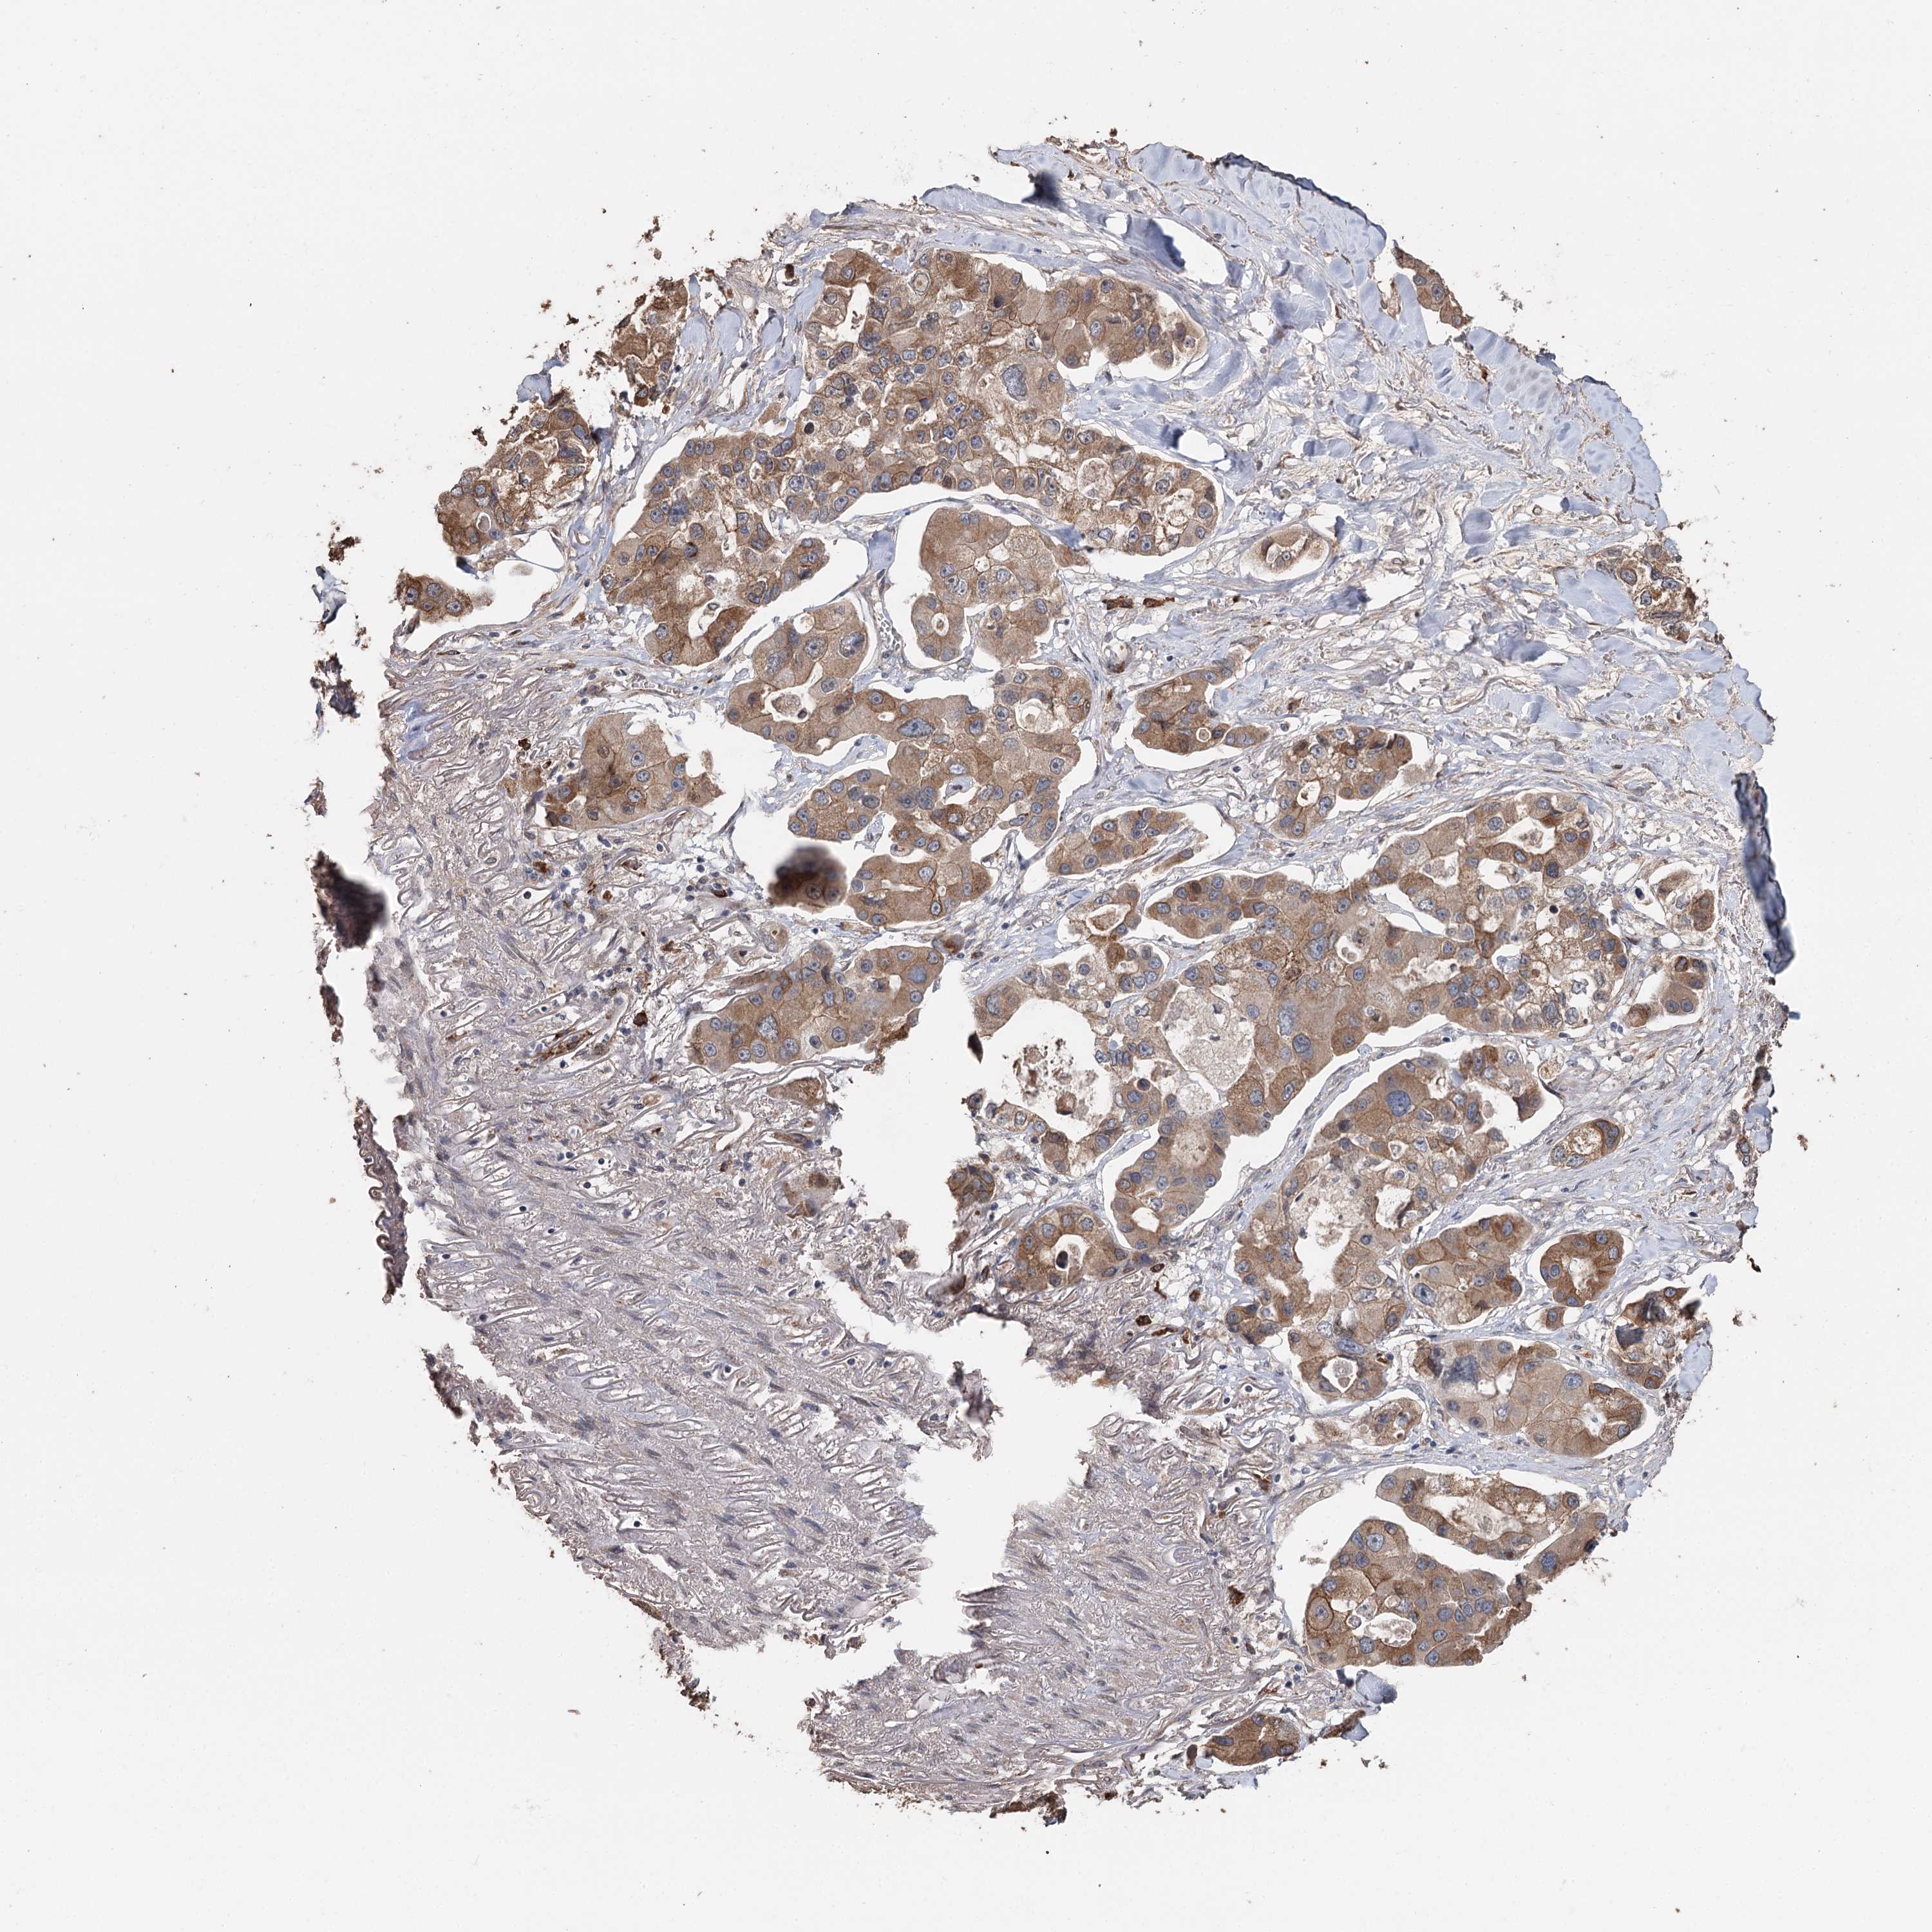

CANCER LUNG CANCER Show tissue menu

Lung cancer

Human cancer

Lung adenocarcinoma

Lung squamous cell carcinoma

SYVN1 is not prognostic in Lung Adenocarcinoma (TCGA)

SYVN1 is not prognostic in Lung Adenocarcinoma (validation)

SYVN1 is not prognostic in Lung Squamous Cell Carcinoma (TCGA)